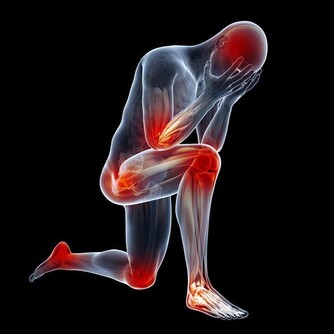

如果把身體比做一台機器,腿就是提供動力的馬達。馬達不靈了,機器便會老化、運轉不良。人老後,不怕頭髮變白、皮膚鬆弛,怕的就是腿腳不靈便。在美國《預防》雜誌總結的長壽跡象中,「腿部肌肉有力」赫然在列。生活中也不難發現,長壽老人幾乎都步履穩健、行走如風。因此,只要養好雙腿,活過百歲的可能性便大大提高。

人老腿先知,腿部的衰老很早就可能表現出來,專家提醒說,如果出現以下情況,就要引起注意了:

腿腳沒有原先靈便了。這是衰老的最早特徵。40歲後,很多人感到腿腳不靈活,稍微多走點路,就像腿上灌滿鉛,發酸發脹,上樓梯也越來越費勁,沒爬幾層就氣喘吁吁。

幹點活就腰酸腿疼。特別是中年女性,只要站的時間一長,就會覺得腰酸腿痛。咳嗽時,腿還會出現放射性疼痛。如果小腿肚出現壓痛更要注意,說明腸胃已經開始「罷工」了。

走路變慢。不知不覺中,步速越來越慢。偶爾走快點,會覺得腿腳不聽使喚,過後會連續酸痛好多天,甚至出現肌肉萎縮的情況。

雙腿一側發涼。即使夏天也總感到小腿肚涼颼颼的,有時還覺得從臀部開始,到腳後跟,中間一條線都涼涼的。這可能是血液循環不暢造成的,也可能和腰椎間盤病變有關。

抽筋次數增多。如果不是在運動後或因為受涼而抽筋,那就要注意了,這可能是骨質疏鬆的表現。有些人還會出現足跟疼痛,也必須引起注意。

腫脹。血液循環不好會導致腿脹,同時這也是心腦血管病或腎臟疾病患者常有的症狀。

靜脈曲張。女性更容易出現這種情況,20歲後就有可能發生。一旦腿上的血管突然非常清晰,彎彎曲曲像蛇一樣,說明腿部血管出現了勞損。

髖膝關節疼痛。幾乎所有關節都會隨著年紀增大而變得脆弱,特別是髖、膝這兩處關節。如果你發現在下樓梯、蹲下或跳躍時出現不適,甚至腿部有摩擦磨損、卡住動不了的感覺,說明關節已經急需保護了。